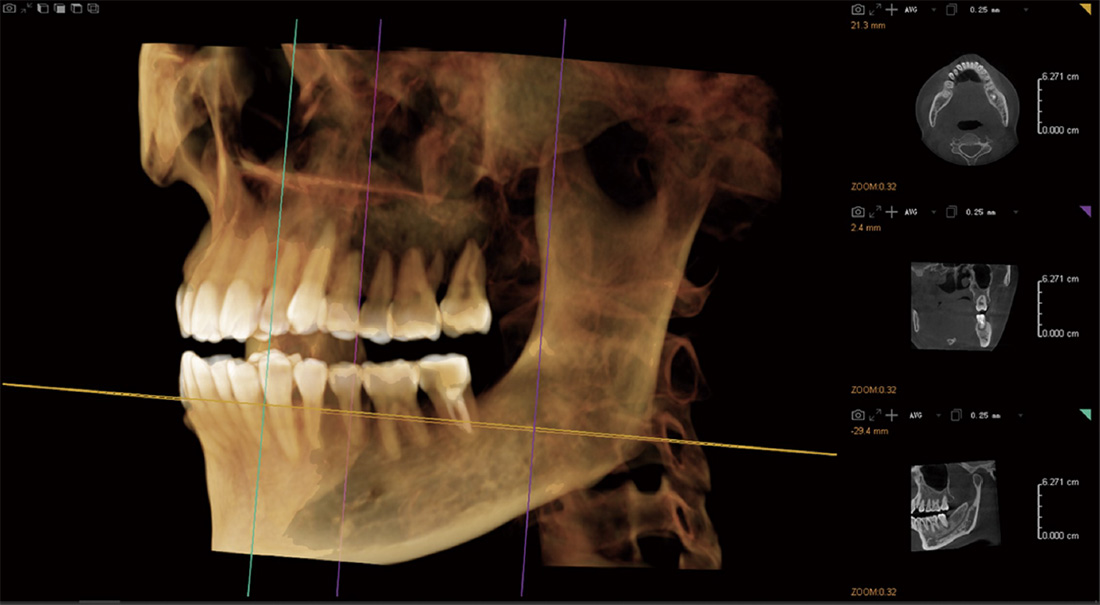

El gran campo de visión D14×10H puede satisfacer todas las necesidades del departamento clínico dental. Se pueden obtener imágenes de toda la dentición, incluida la articulación temporomandibular, en una sola exploración.

Planificación de la cirugia de implantes

Siembra simulada

- DViewMatrix ha agregado un nuevo modulo de implante de simulación 30, que puede medir el ancho, la altura y la densidad ósea de los dientes faltantes y el hueso alveolar, y también puede realizar la delineación del tubo neural.

- Rica biblioteca de implantes

- Introducir parametros de implante simulados y diseñar un plan de implante simulado.

Medición de la densidad ósea

- Medir la osteoporosis y proporcionar referencia para la implantaci6n.